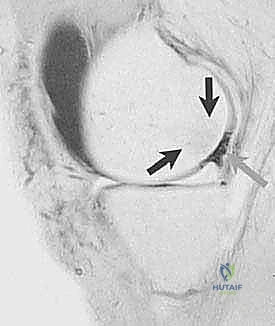

- التصوير بالرنين المغناطيسي (MRI): هو المعيار الذهبي لتشخيص إصابات الغضروف. يوفر صوراً عالية الدقة للأنسجة الرخوة، ويسمح للدكتور هطيف بتحديد حجم، عمق، وموقع العيب الغضروفي بدقة مليمترية، بالإضافة إلى تقييم حالة العظم تحت الغضروفي والأربطة.

- المنظار التشخيصي (Diagnostic Arthroscopy): في بعض الحالات، يكون المنظار الجراحي هو الوسيلة الأدق للتشخيص النهائي وتقييم مدى صلابة الغضروف المحيط بالآفة، حيث يتم إدخال كاميرا دقيقة إلى داخل المفصل لتقييم الوضع على الطبيعة قبل أو أثناء اتخاذ قرار العلاج.